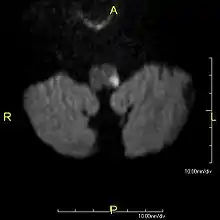

a)High signal in left postero lateral indicates a infarct and thrombosed left vertebral artery b) infarct (circle ) c)indicates absence of normal left vertebral artery ( circle )

Clinical B1000 diffusion weighted MRI image showing an acute left sided dorsal lateral medullary infarct- Abnormal head impulse test, one directional nystagmus, and abnormal skew due to a central vertigo, specifically Wallenberg syndrome